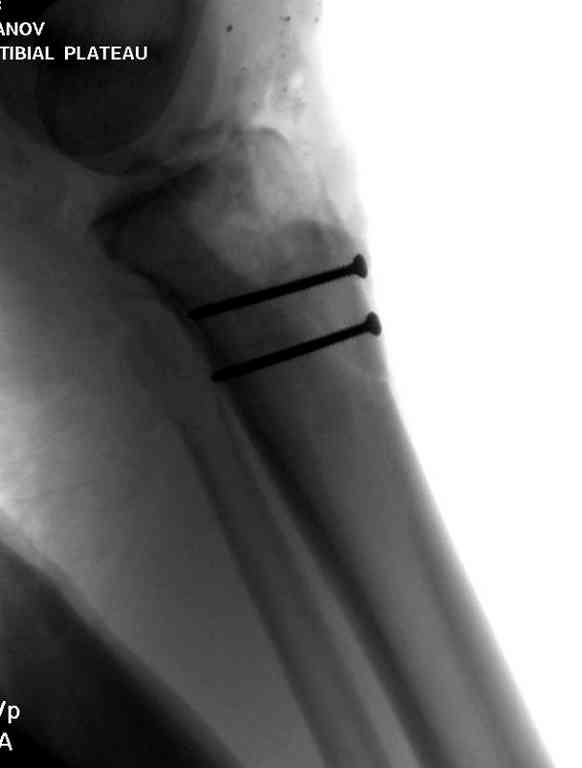

Пожалуйста, снимки.

Коллеги фиксатор Numelock II

На вашем снимке из-за ротации трудно угадать положение пластины, и желательно сделать снимок с захватом верхнего участка бедра.

Одинокий кортикальный шуруп не удержит тибиальный бугор, сустав тибиал плато оставлен без репозиции и фиксации.